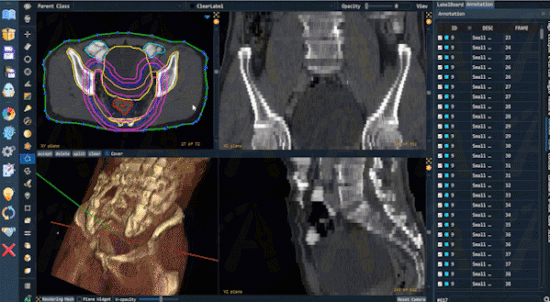

支持放疗勾画的DICOM RT Struct

鉴于放射科对AI研究的重大需求,Pair新增了对放射影像DICOM RT Structure文件格式的全面支持。放射科医生将TPS (Treatment Planning System)放疗规划系统中勾画的放疗靶区轮廓线以RT Struct格式导出后,可直接在Pair中打开,进行可视化和进一步的标注优化。Pair可支持超1000条RT轮廓线的标注交互。Pair更可以将RT Struct内的轮廓线填充并导出成分割标注结果文件,如nii, nii.gz等格式,极大地方便放射科医生使用专业的影像组学软件,如TexRAD、MaZda等,进行后续的高阶分析与研究。